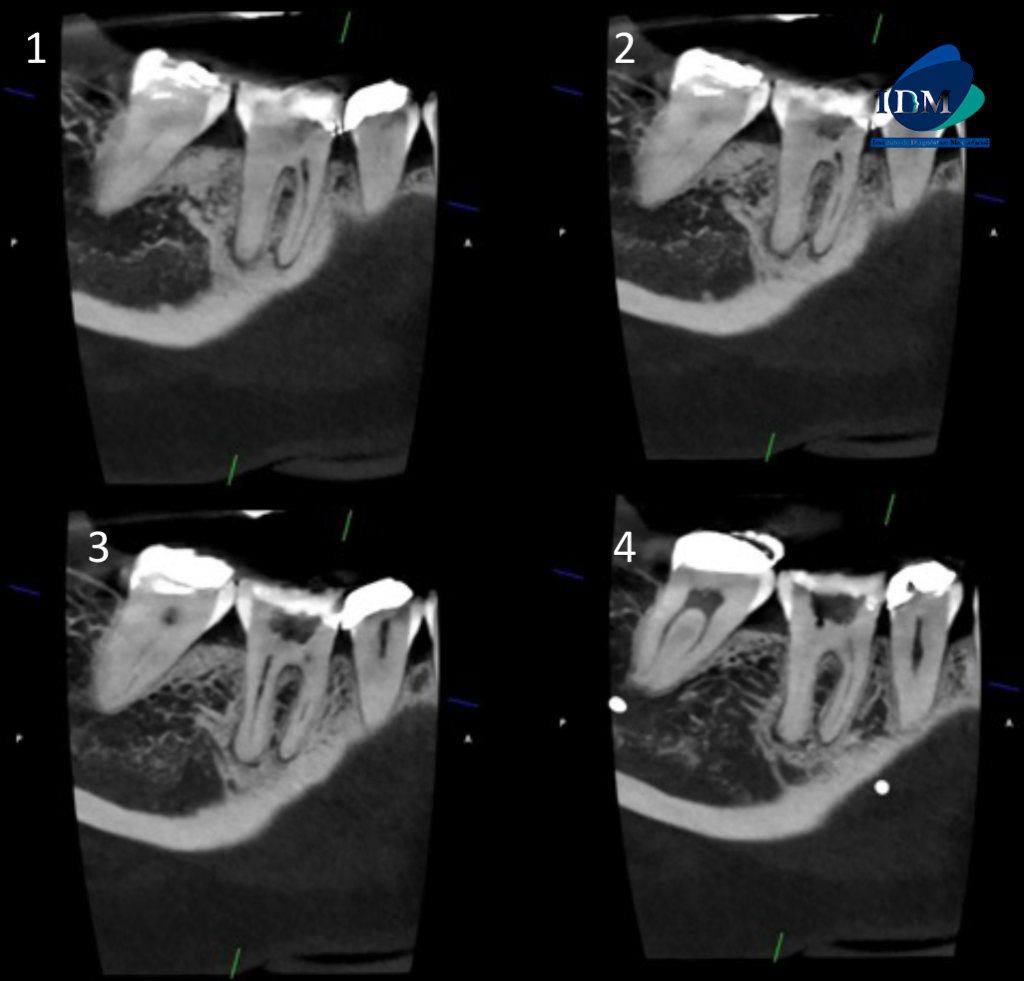

CORTES TRANSAXIALES

A La evaluación de la tomografía computarizada de campo reducido de la pieza 46 se observa material restaurador coronario amplio, una cavidad cameral amplia y ensanchamiento del espacio para el ligamento periodontal periapical en ambas raíces con el aumento de la densidad ósea compatible con osteítis circundante.

Sin embargo respecto a la conformación de los conductos pulpares podemos observar que la raíz mesial presenta un conducto colateral hacia palatino que a su vez confluye con el conducto pulpar principal para nuevamente separarse, todo esto a nivel del tercio apical.